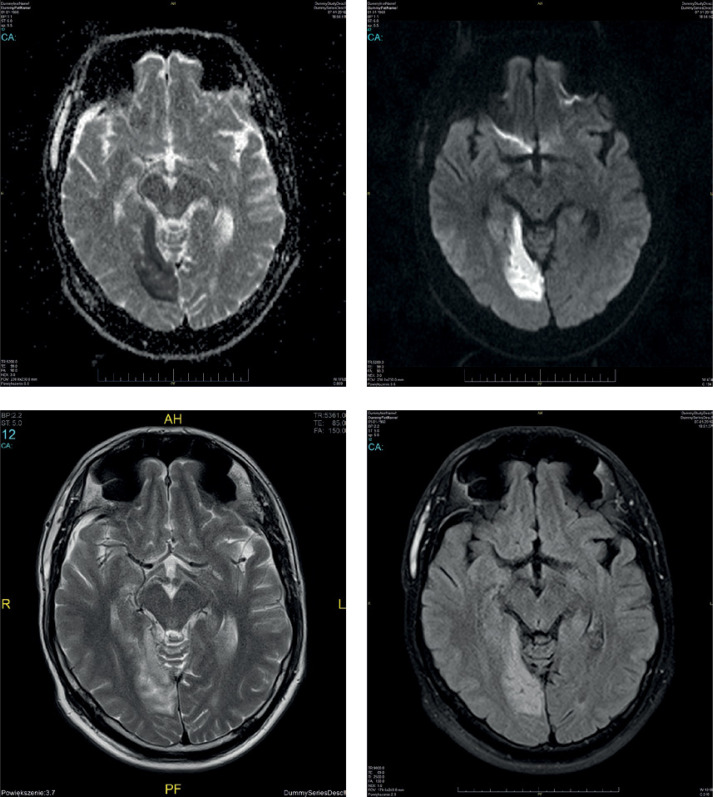

家族性偏瘫性偏头痛男性患者的偏头痛性中风。

Migrainous stroke in a male patient with familial hemiplegic migraine.